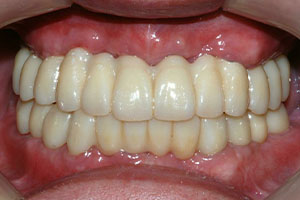

치료증례 전후사진

Before & After